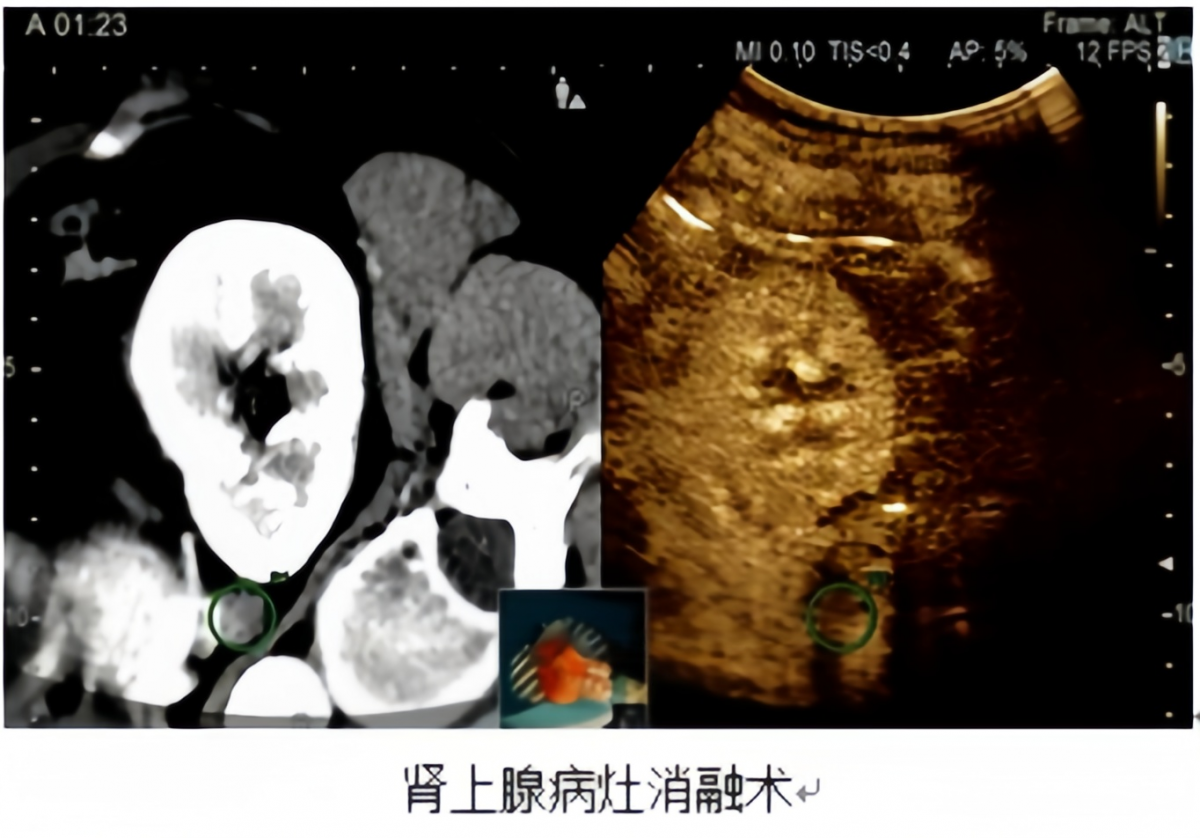

04垂体-肾上腺-性腺亚专科

★精准诊疗,攻克疑难

垂体、肾上腺、性腺疾病表现复杂隐匿,常以继发性高血压、发育异常、激素瘤等形式出现,属于内分泌领域的疑难重症。

依托医院高水平影像与检验平台,垂体-肾上腺-性腺亚专科常规开展多项国内领先的功能定位与微创技术。

精准定位:开展岩下窦静脉采血、肾上腺静脉采血等“金标准”技术,精准判断病变来源。

微创治疗:对符合条件的肾上腺良性肿瘤实施消融术,以针代刀,创伤小、恢复快,该项特色技术达到全省的领先水平。